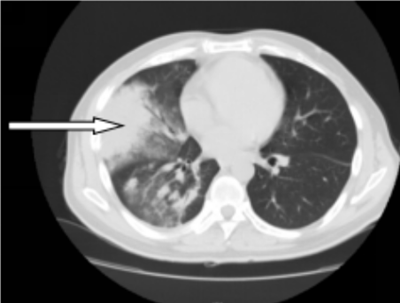

41岁的彭先生,2022年3月份出现咳嗽咳痰,多家医院治疗效果不佳,外院查胸部CT提示肺部占位及大量胸水,且外周血白细胞明显升高及颈部多发的淋巴结肿大。4月初疑诊结核收入我院结核科,入院后发现浅表淋巴结进行性增大,经血液科会诊,考虑淋巴瘤并骨髓侵犯。患者转入血液内科后,行骨髓涂片提示有77%肿瘤细胞,同时请耳鼻喉科行颈部淋巴结切除病检,最终确诊为低级别滤泡性淋巴瘤并肺部、骨髓侵犯(IV期,EZH2基因突变阴性)。4月27日根据最新的滤泡性淋巴瘤诊治指南(NCCN指南及CSCO指南),选用GB方案(奥妥珠单抗联合苯达莫司汀)化疗。第一周期化疗后,彭先生状态良好。5月26日复查肺部CT,肺部占位、胸水及淋巴结明显缩小。咳嗽及气促也完全消失。目前,患者仍在血液内科接受后续治疗。

图一:4月10日化疗前肺部CT,箭头所指肺部为淋巴瘤浸润引起的肺实变(胸水已引流)